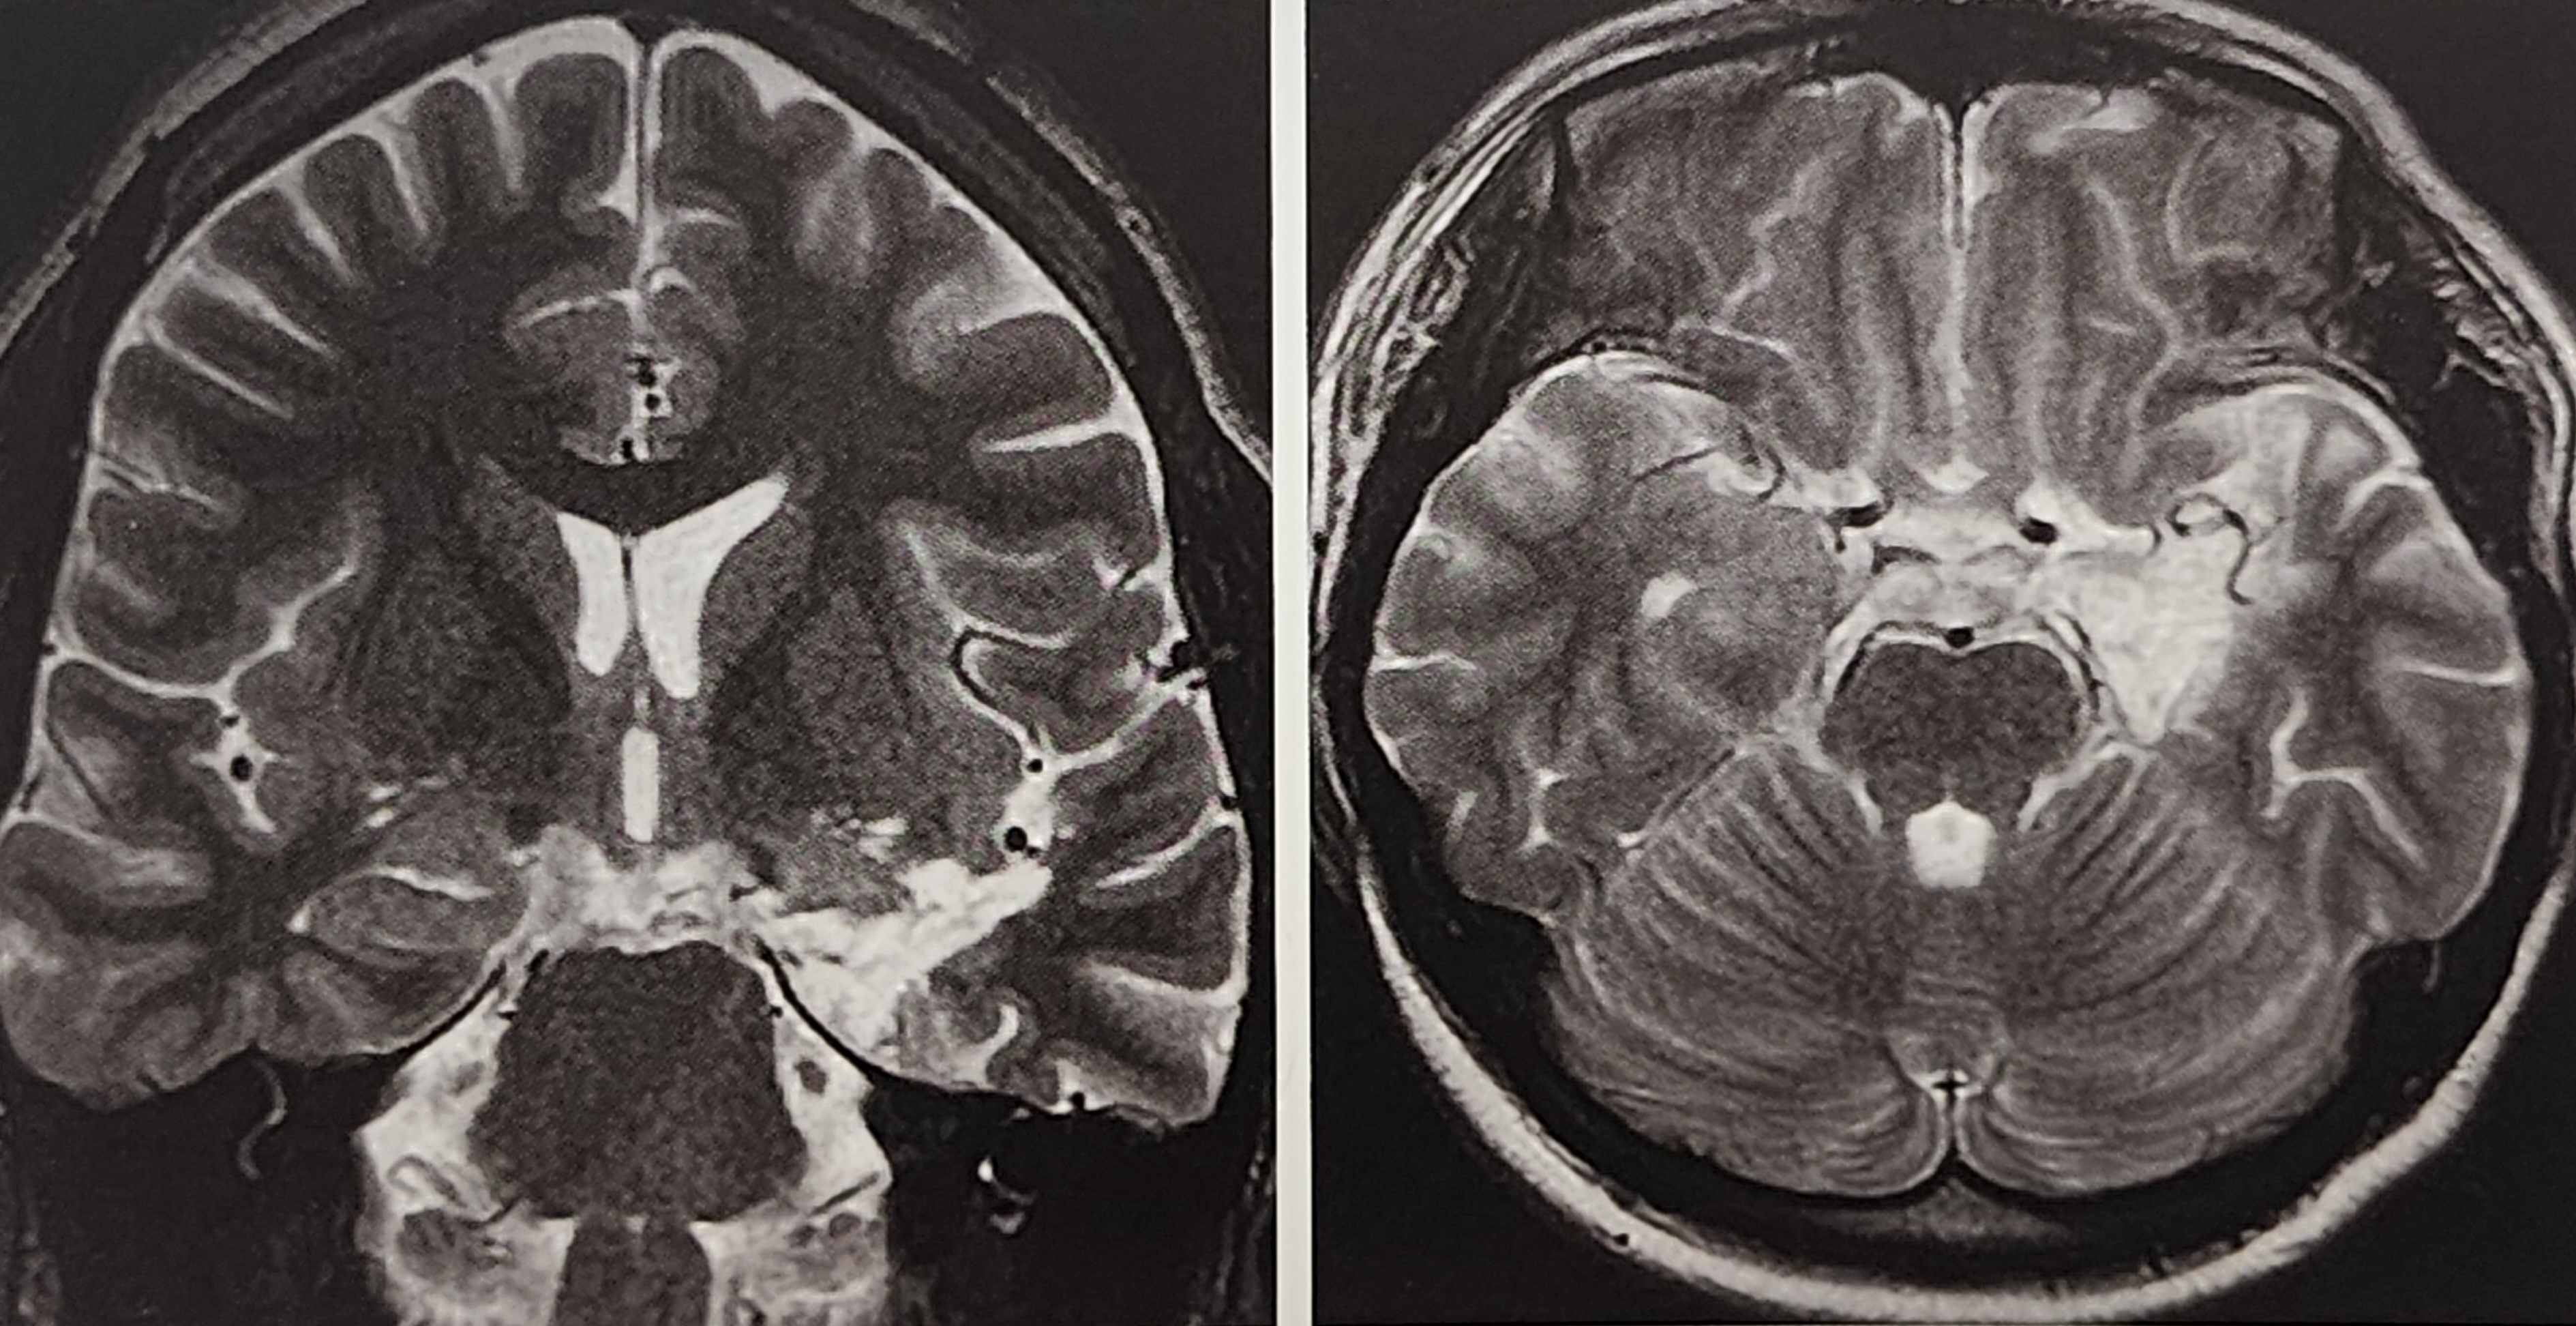

3.1 MRI(자기공명영상) 검사

MRI는 해마경화증이나 측두엽 구조 이상을 확인하는 가장 중요한 검사법이다. 특히 FLAIR(Fluid-Attenuated Inversion Recovery) 기법을 사용하여 뇌조직의 손상을 더욱 명확히 확인할 수 있다.